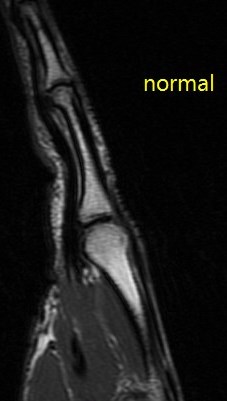

Figure 2 for case A2 pulley rupture finger (RID2437)

Figure 2

Imaging in flexion helps bring out this abnormality. The hand surgeon specifically requests it now. Also I ask the technologist to always include an adjacent normal finger for comparison.

A2 pulley rupture finger (RID2437)